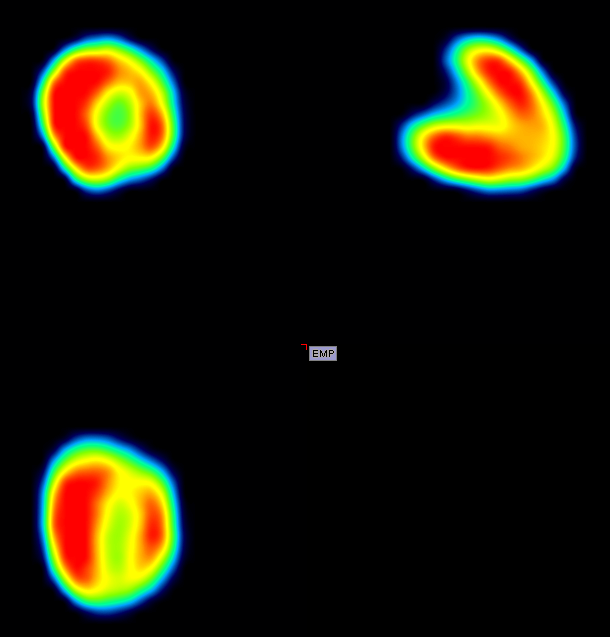

Rabbit with weight of 181g, 18F-FDG NR_iter15_sub_1 4床位拼床

330g 兔子耳缘静脉注射18F-FDG 1.03mCi 60分钟后,每床位采集15分钟,共3床位 / 195g 兔子耳缘静脉注射18F-FDG 190uci 35分钟后,单床位采集2小时